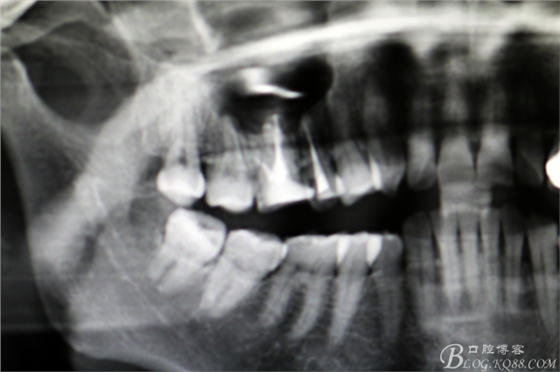

圖3.根尖片顯示15、16根管治療已經(jīng)完成,16腭根牙膠尖超填,15、16根尖區(qū)橢圓形陰影

圖4.全景片影像檢查:以16為中心的橢圓形陰影,當(dāng)時(shí)15未作根管治療。